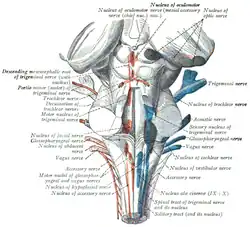

Cross section of the midbrain at the level of the superior colliculus showing oculomotor nucleus . Scheme showing central connections of the optic nerves and optic tracts.

Scheme showing central connections of the optic nerves and optic tracts. Cross section of the pons at the level of the facial colliculus. PPRF is not labeled, but is visible adjacent to the abducens nucleus